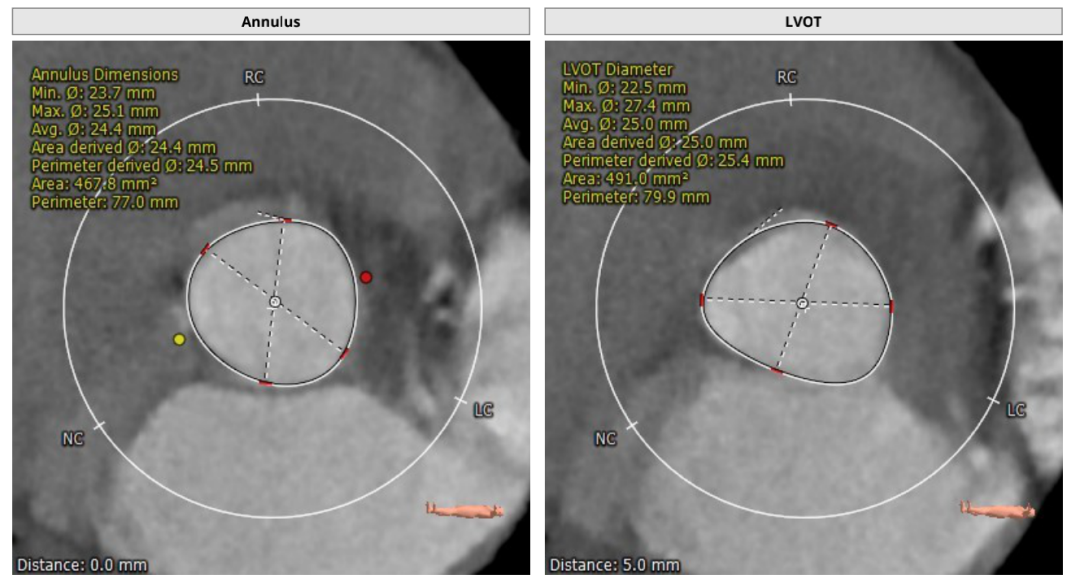

CT评估

瓣环直径:24.5mm,左室流出道直径:25.4mm

主动脉窦:25.9*36.9mm,STJ:30.4mm

升主动脉直径:36.5,心脏夹角:59度

左冠高度:20.1mm,右冠高度:19.5mm